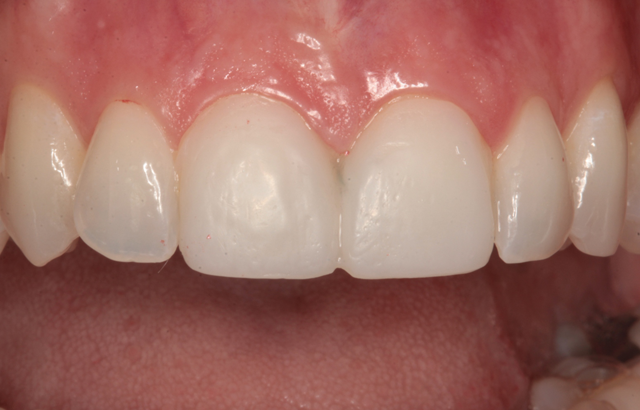

The final result is shown from the incisal view in Figure 27. The facial view after treatment can be seen in Figure 28. The patient's new smile is shown in Figure 29.

Fig. 27 Fig. 28

By using team treatment, Peter and I were able to achieve a superb color match with ceramic veneers that mimicked the appearance the surrounding neighbors. It was my job to prepare the teeth properly, acquire accurate impressions, provide excellent photography, choose a shade and deliver the finished laminates. Peter's job was to pour accurate models, produce the ceramic veneers and develop the color and contours to achieve the esthetic result.